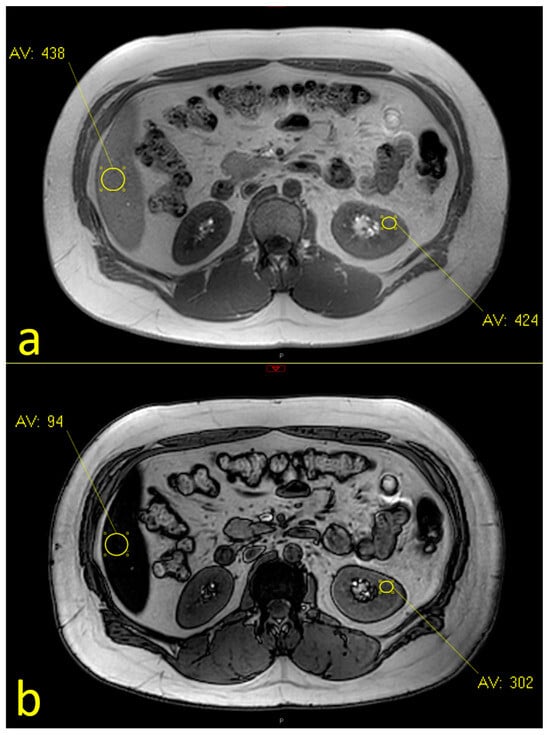

2.2. MRI Assessment